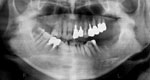

では、CTで撮影したものがどう見えるのかご覧下さい。

まだまだ、神経や血管の位置がよくわかりません。

神経、血管は大きいものが一本と言われていますが、実際は個人差があり、小さい血管神経も含めると、複数あると報告されています。

実際にCTで撮影し、「CTデータ3D立体構築画像変換検査」したものがどう見えるのがご覧下さい。CTデータ3D立体構築画像変換検査した場合、3次元でどこにどのようにインプラントを埋め込んでいけばいいのか、立体的に把握することができます。